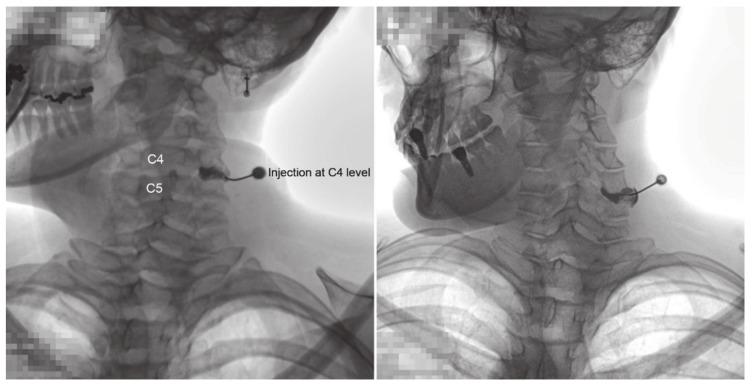

Cervical facet joint (CFJ) syndrome is a common cause of neck pain. For its diagnosis and treatment, CFJ injection with arthrogram is generally performed. This study aimed to investigate the frequency of extra-CFJ flow on CFJ arthrograms during injections and its differences according to age, sex, and cervical vertebral level. We analyzed 760 CFJ arthrograms administrated to 208 patients diagnosed with CFJ syndrome. Arthrograms at each vertebral level were collected to evaluate the normal CFJ and extra-CFJ flow. The primary and secondary outcomes were frequency of extra-CFJ flow according to cervical vertebral level, age, and sex and according to pairwise cervical levels, respectively. Extra-CFJ flow at the cervical spine occurred during 179 injections, and the overall incidence was 3.3-36.2% at different cervical levels. The incidence of extra-CFJ flow at each cervical vertebral level according to age and sex was not significant. Extra-CFJ flow was the highest at C6 and C7, but there was no statistical significance. Extra-CFJ flow was higher at lower vertebral levels (C5-C7) than at upper levels (C3 and C4). Additional clinical studies and anatomical evaluations are needed to support its clinical value and enable the development of new injection techniques.

颈椎小关节(CFJ)综合征是颈部疼痛的常见原因。对于其诊断和治疗,一般进行CFJ注射造影。本研究旨在调查注射过程中CFJ造影时CFJ外造影剂流动的频率及其根据年龄、性别和颈椎节段的差异。我们分析了208例诊断为CFJ综合征患者的760份CFJ造影。收集每个颈椎节段的造影以评估正常CFJ和CFJ外造影剂流动。主要和次要结局分别是根据颈椎节段、年龄和性别以及成对颈椎节段的CFJ外造影剂流动频率。颈椎CFJ外造影剂流动发生在179次注射中,不同颈椎节段的总体发生率为3.3% - 36.2%。根据年龄和性别,每个颈椎节段CFJ外造影剂流动的发生率无显著差异。CFJ外造影剂流动在C6和C7处最高,但无统计学意义。CFJ外造影剂流动在较低颈椎节段(C5 - C7)高于较高颈椎节段(C3和C4)。需要进一步的临床研究和解剖学评估来支持其临床价值并推动新注射技术的发展。